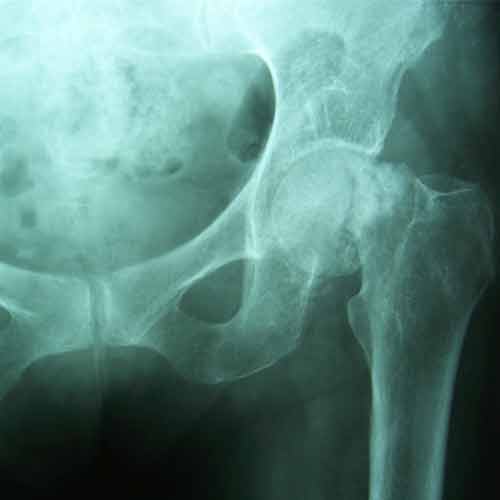

Case:11 Fracture Intracapsular Neck Femur

80 years old female patient treated with bipolar prosthesis.

Pre-Op

Post-op